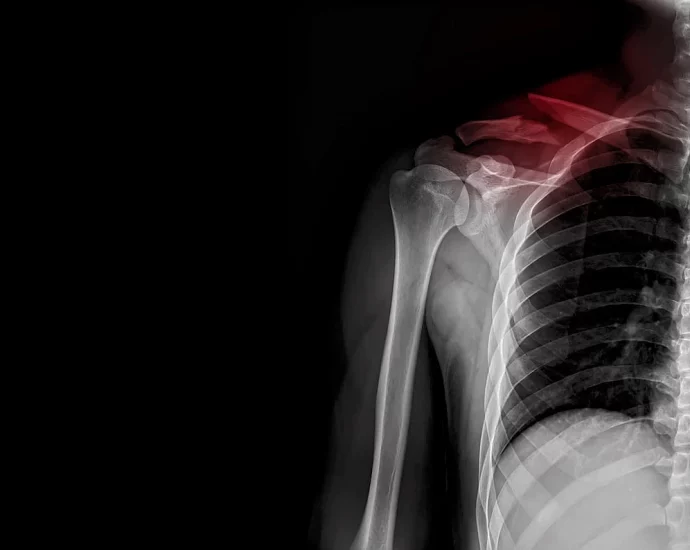

Skipping Breakfast? Beware Broken Bones, Study Says

FRIDAY, Aug. 29, 2025 (HealthDay News) — Breakfast is said to be the most important meal of the day, and a new study says that’s absolutely true as far as bone health is concerned. Folks who skip breakfast have a greater risk of broken bones from osteoporosis, researchers reported Aug.Continue Reading